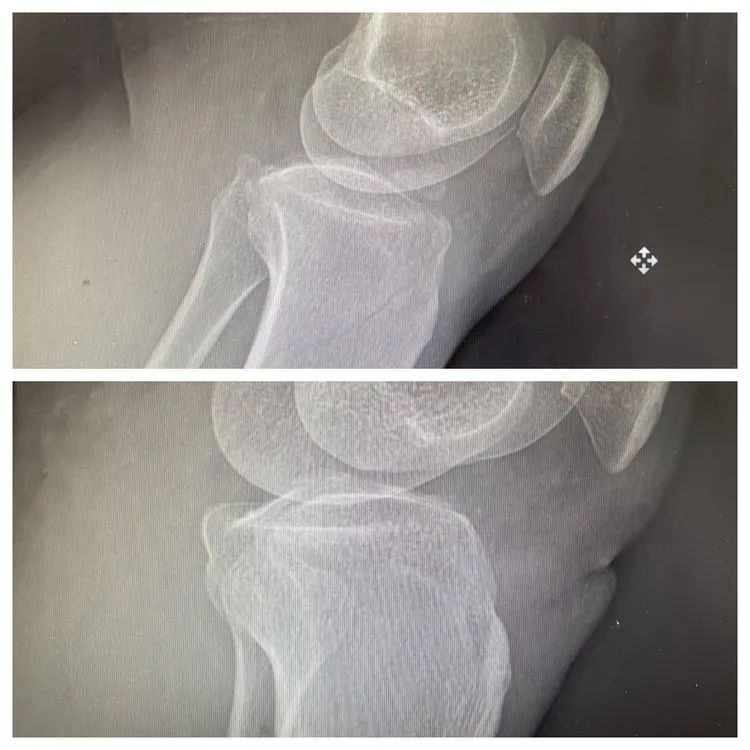

患者李女士在家不慎摔伤左膝关节,门诊查体摄片显示:左胫骨平台骨折,遂入院治疗。胡红耘副院长、吴在顶主任、吴启明副主任带领医生们详细分析了李女士的病情,认为必须手术治疗。李女士立刻反对:“这是膝盖,绝对不能手术,别人都说,膝盖做了手术就站不起来了。”吴在顶主任耐心安抚李女士:“我们使用的是关节镜手术,这种手术创伤小、痛楚少、恢复快,不是您想象的那种‘开大刀’!”随后,吴主任又向李女士展示了骨科之前做过的几例膝关节手术,李女士才安下心来。

入院第4天,骨科团队为李女士做了膝关节镜检+关节清理+骨折内固定术,手术十分顺利,李女士的膝盖上只留下了一个钥匙孔大小的伤口,并很快愈合。李女士惊叹:“没想到微创手术真的是微创,这伤口也太小了!而且我几乎都没感觉到什么疼痛,你们这技术值得一个大大的赞!”

84岁的迟奶奶摔伤导致右髋部疼痛伴活动受限,门诊摄片显示右股骨粗隆间骨折,遂收治入院。为缓解老人的痛苦,骨科团队决定尽快进行手术治疗。但是老人年纪大,基础疾病多,身体质素差,但是骨科团队凭借高超的技术、丰富的经验,为迟奶奶进行了右股骨粗隆间闭合复位髓内钉固定手术。手术非常成功,患者恢复良好。在住院恢复期间,骨科医护们时常到迟奶奶床边,陪她开开玩笑,给她说说注意事项,缓解她的忧虑。迟奶奶的儿女看到医护人员态度这么好,内心充满感动,多次提出要请医护们吃饭,都被婉拒,吴在顶主任说:“你们信任我们,就是对我们最大的褒奖。治疗好、护理好都是我们该做的!”